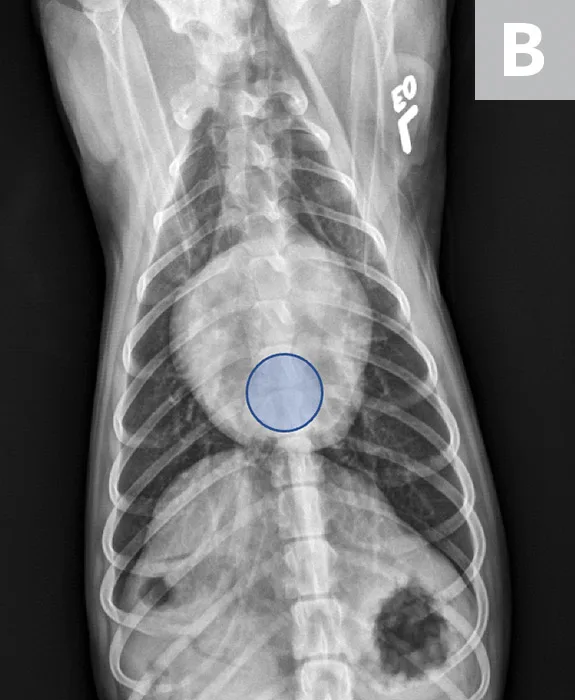

FIGURE 1

VLAS measurement in a dog with suspected stage B1 MMVD using a left lateral radiograph (A). A caliper was used to measure from the center of the most ventral aspect of the carina to the most caudal aspect of the left atrium, where it intersects with the dorsal border of the caudal vena cava. This measurement was transferred to the cranial aspect of T4 and extended caudally along the thoracic vertebrae. The number of vertebrae this line transversed was rounded to the nearest tenth to determine VLAS (2.1 VBUs). Stage B1 MMVD was confirmed via echocardiography. A redundant dorsal tracheal membrane, gastric food/foreign material, and mild T3 to T4 spondylosis deformans can also be seen. An orthogonal radiograph of the patient provides a more complete evaluation of cardiac silhouette (B); normal location of the left atrium is indicated (circle).

FIGURE 2

VLAS measurement in a dog with suspected stage B2 MMVD using a right lateral radiograph (A). A caliper was used to measure from the center of the most ventral aspect of the carina to the most caudal aspect of the left atrium, where it intersects with the dorsal border of the caudal vena cava. This measurement was transferred to the cranial aspect of T4 and extended caudally along the thoracic vertebrae. The number of vertebrae this line transversed was rounded to the nearest tenth to determine VLAS (2.8 VBUs). Stage B2 MMVD was confirmed via echocardiography. Other structures are unremarkable. An orthogonal radiograph of the patient provides a more complete evaluation of cardiac silhouette (B); normal location of the left atrium is indicated (circle).